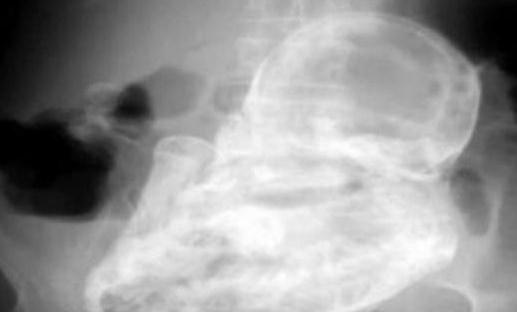

不过,接下来的发现却让所有人吓了一大跳——老太太的子宫外竟然有个未发育的胎儿,但已经死亡了近40年。

这个“石化胚胎”是怎么形成的呢?医生解释称:“由于胚胎未在子宫里发育,移动到老妇的腹腔,导致胚胎无法正常生长,因而钙化形成石胎。”